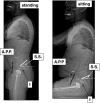

Methods: This analysis, based on innovative radiologic methods as the EOS(®) technology but also on a new look at conventional imaging makes it possible to better analyze standing lateral images and seated images.

Results: Disturbances can come from atypical morphotypes or from unusual postures as in aging spine. The measurement of available extension and the concept of available flexion provide new information regarding individual's adaptation to the imbalance induced by disorders of the spine or lower limbs.